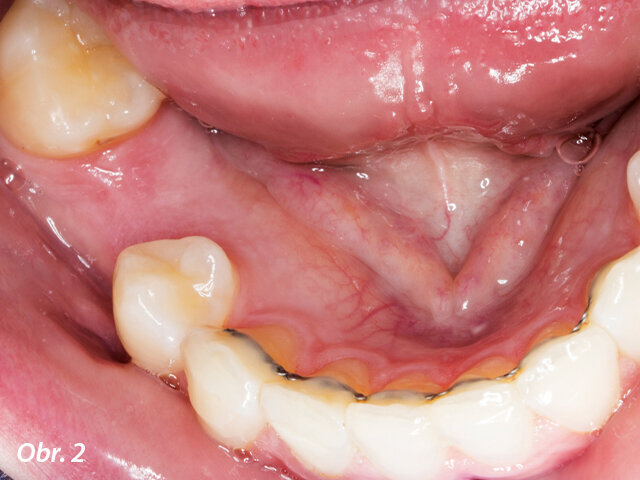

Dolní zuby pacientky před ošetřením.